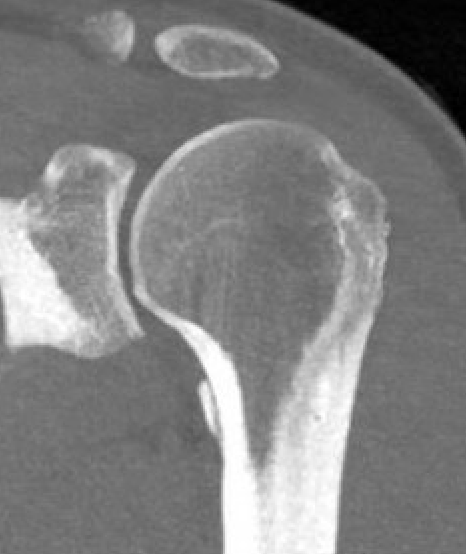

Bony avulsions (BHAGL)

BHAGLBHAGLBHAGL

Bony avulsion HAGL